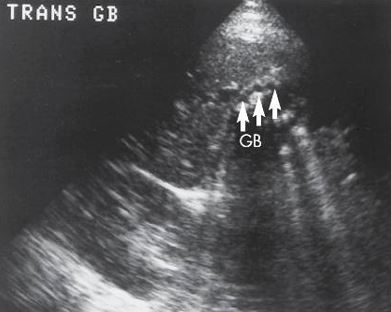

black: cystic duct

white: valves of heister

what are the arrows pointing to?

cystic duct